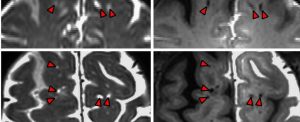

به گزارش دانشجو کارکرد درونی سیستم دفع ضایعات مغز ما سرانجام بعد از سالها گمانهزنی بهواسطه پژوهش روی مایع مغزی...